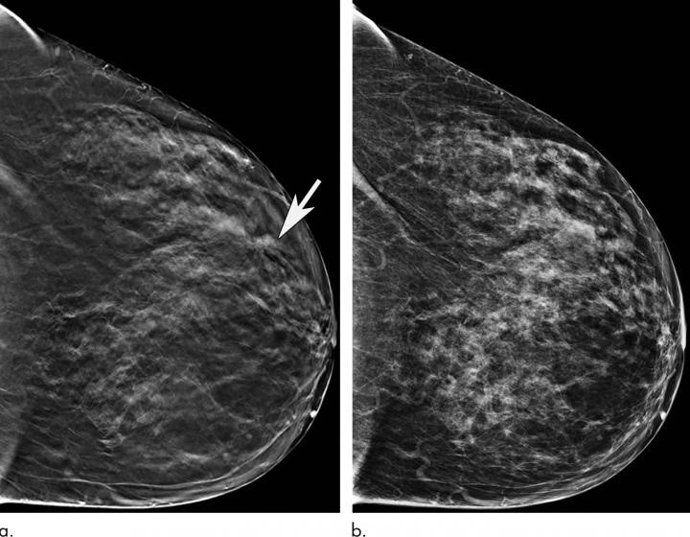

Archivo - Arxiu - Les dones majors es beneficien significativament quan es fan examinacions amb una mamografia 3-D